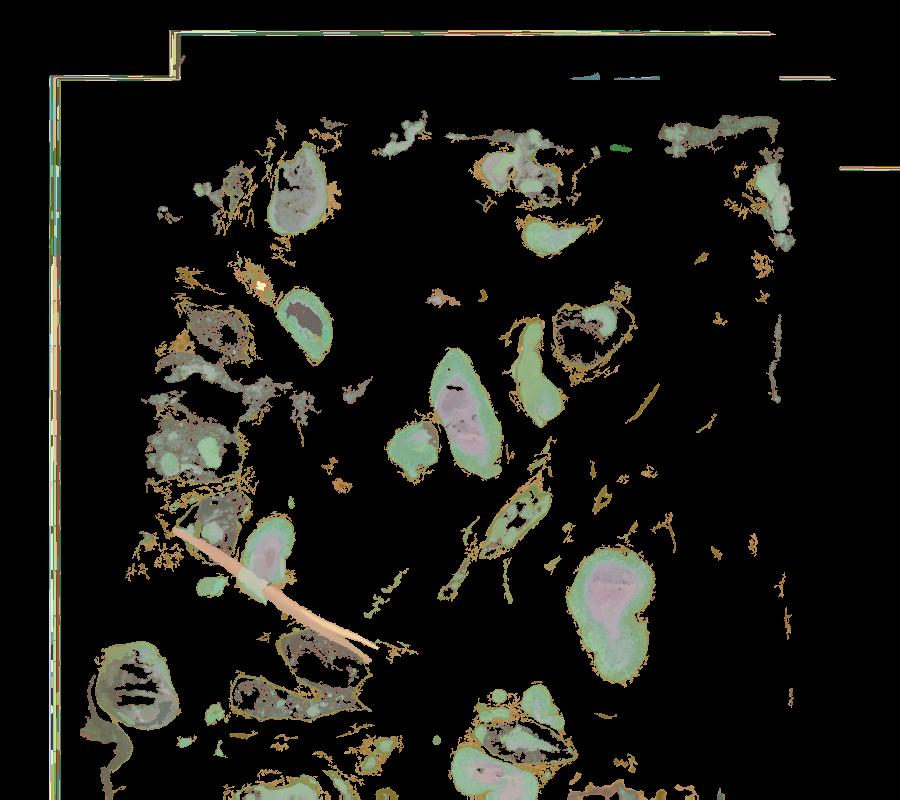

Atlas: Washington University

Breast cancer (BC) is defined by distinct molecular subtypes with different cells of origin. The transcriptional networks that characterize the subtype-specific tumor-normal lineages are not established. In this work, we applied bulk, single-cell and single-nucleus multi-omic techniques as well as spatial transcriptomics and multiplex imaging on 61 samples from 37 patients with BC to show characteristic links in gene expression and chromatin accessibility between BC subtypes and their putative cells of origin. Regulatory network analysis of transcription factors underscored the importance of BHLHE40 in luminal BC and luminal mature cells and KLF5 in basal-like tumors and luminal progenitor cells. Furthermore, we identify key genes defining the basal-like (SOX6 and KCNQ3) and luminal A/B (FAM155A and LRP1B) lineages. Exhausted CTLA4-expressing CD8+ T cells were enriched in basal-like BC, suggesting an altered means of immune dysfunction. These findings demonstrate analysis of paired transcription and chromatin accessibility at the single-cell level is a powerful tool for investigating cancer lineage and highlight transcriptional networks that define basal and luminal BC lineages.